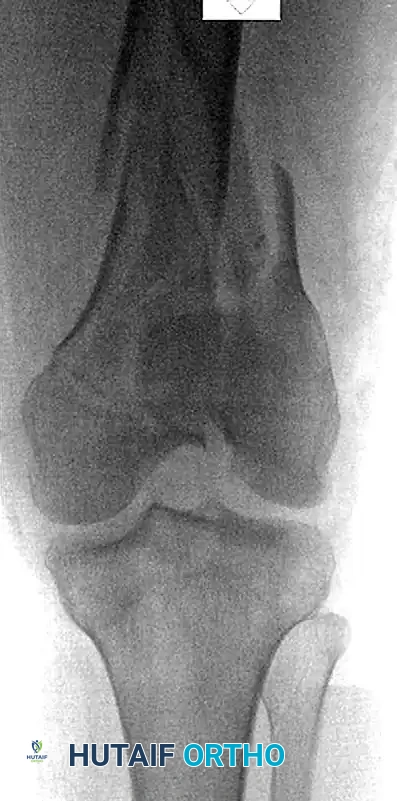

Preoperative radiograph demonstrating a highly comminuted distal femoral fracture in a pedestrian struck by a high-speed vehicle. Note the very low fracture involvement of the medial femoral condyle. Lateral-based constructs alone would typically fail to provide adequate fixation into this specific fragment.